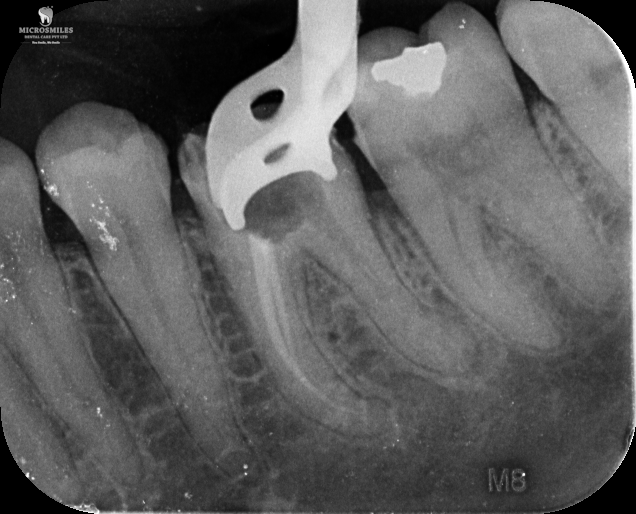

Our treatments are performed using advanced dental microscopes that magnify up to 25x- allowing us to identify previously hidden canals, fractures, or infected areas that standard tools may miss. This level of detail means faster, more accurate procedures and fewer surprises, giving your tooth the attention it truly deserves.

We streamline the retreatment process by using enhanced imaging, digital diagnostics, and precision tools-reducing unnecessary visits and helping you get back to normal faster.